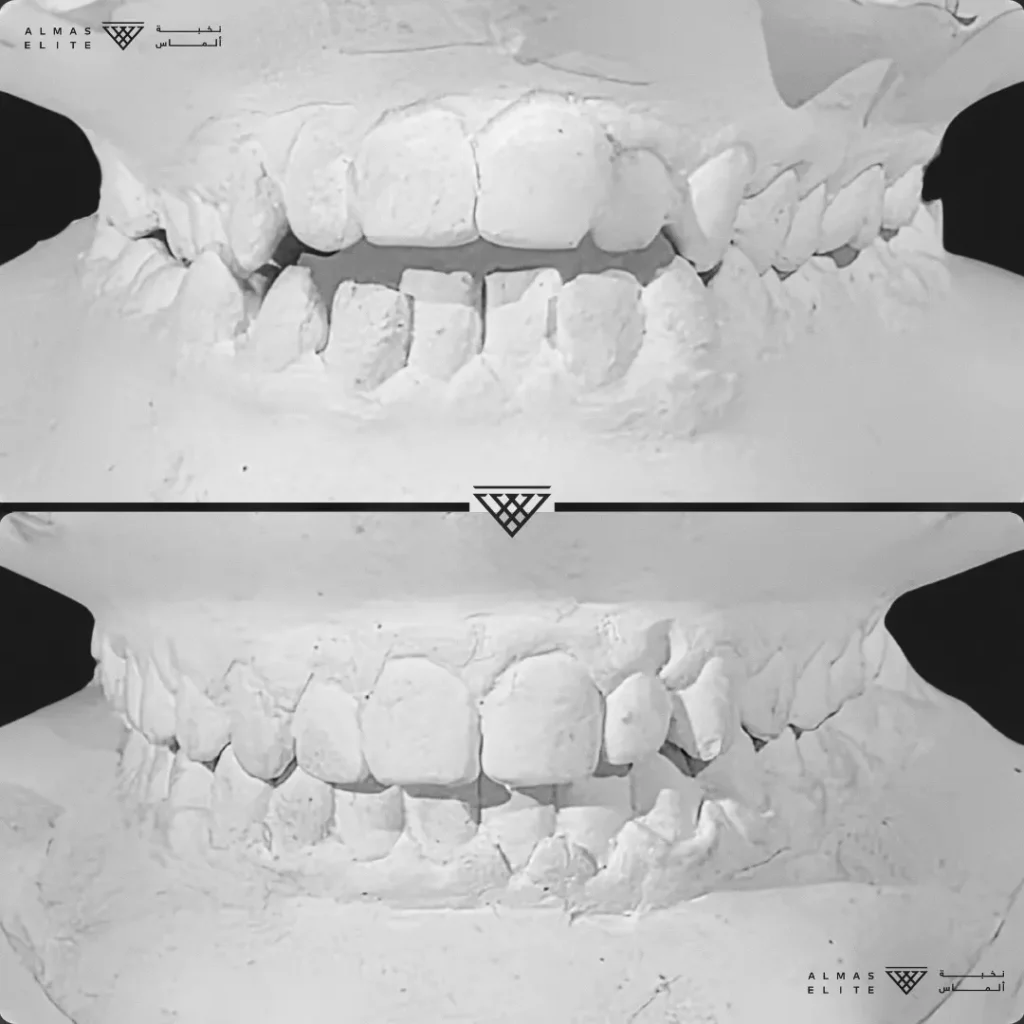

- تشخيص دقيق يشمل الأشعة والتحليل الرقمي للأسنان والفكين.

٢) التقييم والتشخيص الشامل

يشمل صور الأشعة والتحليل الرقمي للأسنان والفكين للوصول إلى تشخيص دقيق.

٣) وضع خطة علاجية مخصصة

تتضمن نوع الجهاز الأنسب، المدة المتوقعة، وتكلفة العلاج، مع شرح واضح لما يمكن توقعه أثناء رحلة التقويم.